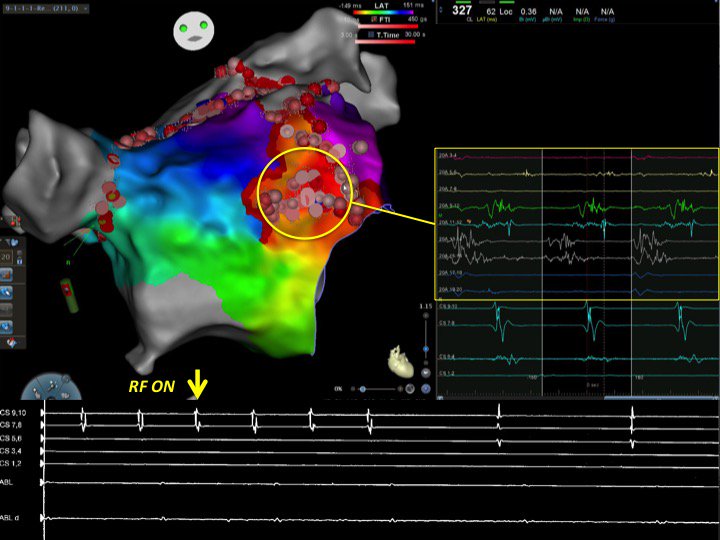

Micro-reentrant AT in the anterior LA during persistent AF ablation following PVI, anterior mitral isthmus and roof lines. All EGMs of the Pentaray (yellow circle) encompass the TCL. Focal ablation in this area terminated the AT. #HowcoolisEP #HDmapping

DrAJRestrepo's tweet image. Micro-reentrant AT in the anterior LA during persistent AF ablation following PVI, anterior mitral isthmus and roof lines. All EGMs of the Pentaray (yellow circle) encompass the TCL. Focal ablation in this area terminated the AT. #HowcoolisEP #HDmapping